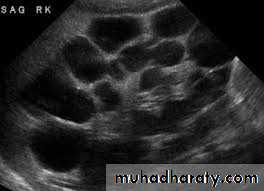

Classification of hydronephrosis in grade I–IV.

• Hydronephrosis grade I: dilatation of the renal pelvis without dilatation of the calices without signs of parenchymal atrophy. • Hydronephrosis grade II: dilatation of the renal pelvis and calices. No signs of parenchymal atrophy. • Hydronephrosis grade III: Minor signs of organ atrophy present (flat papillae and blunt fornices).• Hydronephrosis grade IV: massive dilatation of the renal pelvis and calices. Significant signs of renal atrophy (thin parenchyma).

7.Renal agenesis8.Polycystic disease of the kidney infantile(AR) usually presented in the first few days of life with renal failure and enlarged kidneys . Adult(AD) presented in the third decade with loin pain, hematuria hypertension and renal failure , 25-50% have positive family history . It is most invariably bilateral , diagnosed by US or CT

The principle feature is dilatation of the PCS and ureter.US show hydronephrosis